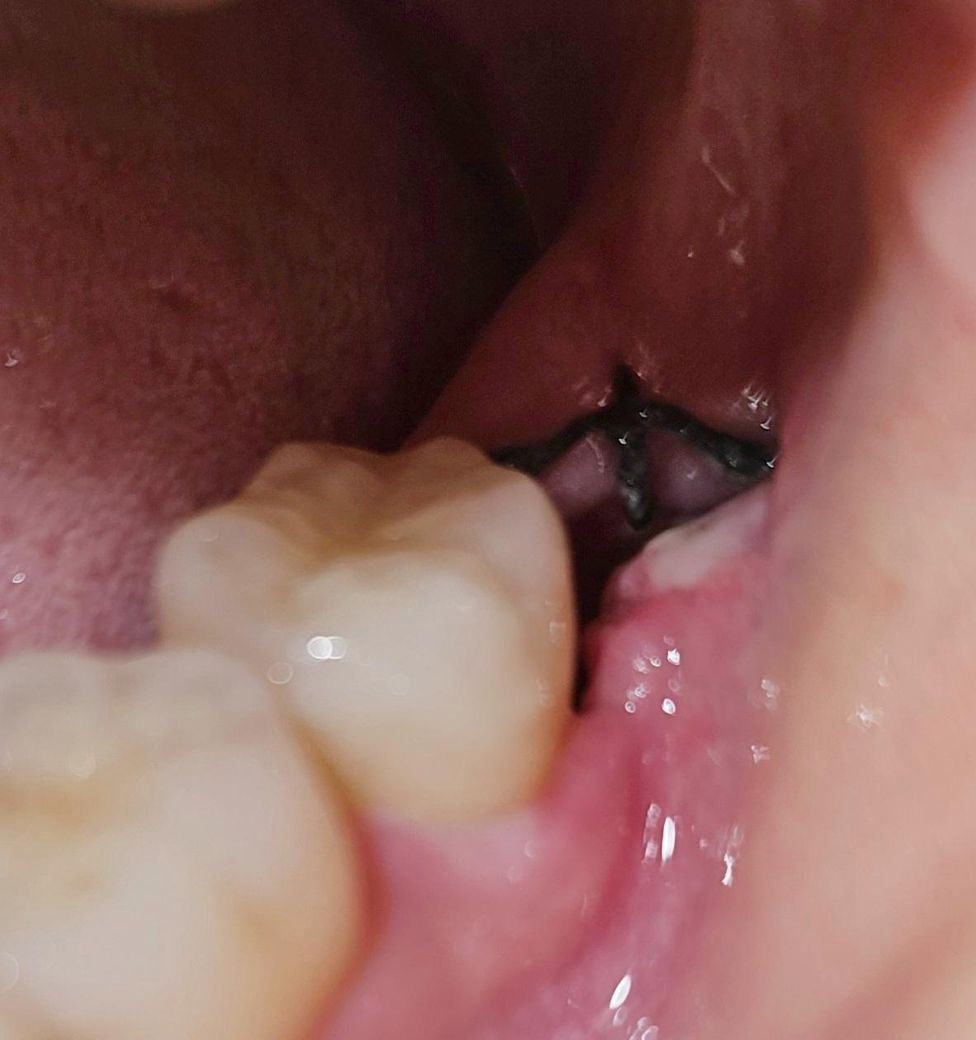

발치한지 5일 차인 오늘 촬영한

해당 부위의 사진들을 보시고

드라이소켓(건성발치와)인지 한번 봐주신다면

감사하겠습니다.

• 2번 째 사진